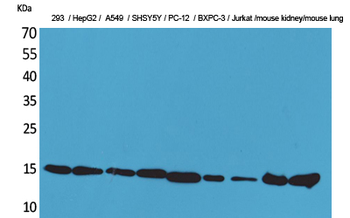

10 μg, 100 μgCYPA Rabbit Polyclonal Antibody [orb100498]

FC, IF, IHC-Fr, IHC-P, WB

Bovine, Canine, Porcine, Rabbit

Human, Mouse, Rat

Rabbit

Polyclonal

Unconjugated

50 μl, 100 μl, 200 μlFKBP52 Antibody: APC [orb147210]